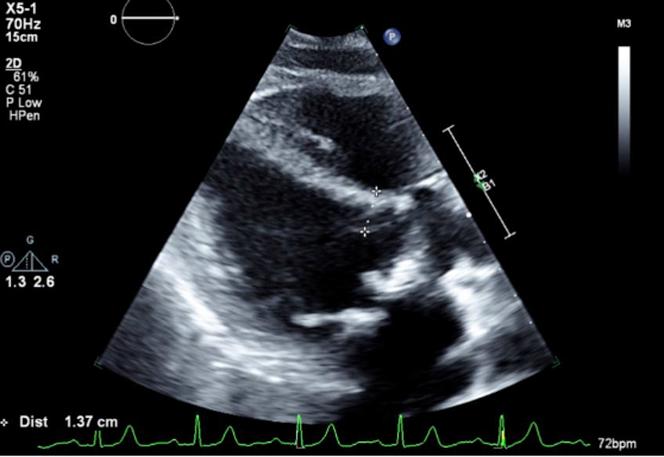

Left ventricular outflow tract obstruction (LVOTO) can complicate percutaneous mitral valve replacement and may preclude patients considered high surgical risk from transcatheter therapies. We report a case of mitral valve-in-valve procedure in a patient at high risk for LVOTO. ().

左心室流出道梗阻(LVOTO)会使经皮二尖瓣置换术变得复杂,并且可能使那些被认为手术风险高的患者无法接受经导管治疗。我们报告了一例左心室流出道梗阻高风险患者进行瓣中瓣手术的病例。()